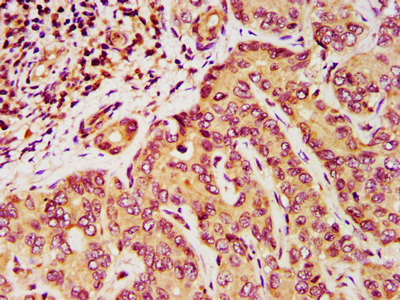

IHC image of CSB-PA007147LA01HU diluted at 1:200 and staining in paraffin-embedded human liver cancer performed on a Leica BondTM system. After dewaxing and hydration, antigen retrieval was mediated by high pressure in a citrate buffer (pH 6.0). Section was blocked with 10% normal goat serum 30min at RT. Then primary antibody (1% BSA) was incubated at 4°C overnight. The primary is detected by a biotinylated secondary antibody and visualized using an HRP conjugated SP system.

IHC image of CSB-PA007147LA01HU diluted at 1:200 and staining in paraffin-embedded human ovarian cancer performed on a Leica BondTM system. After dewaxing and hydration, antigen retrieval was mediated by high pressure in a citrate buffer (pH 6.0). Section was blocked with 10% normal goat serum 30min at RT. Then primary antibody (1% BSA) was incubated at 4°C overnight. The primary is detected by a biotinylated secondary antibody and visualized using an HRP conjugated SP system.